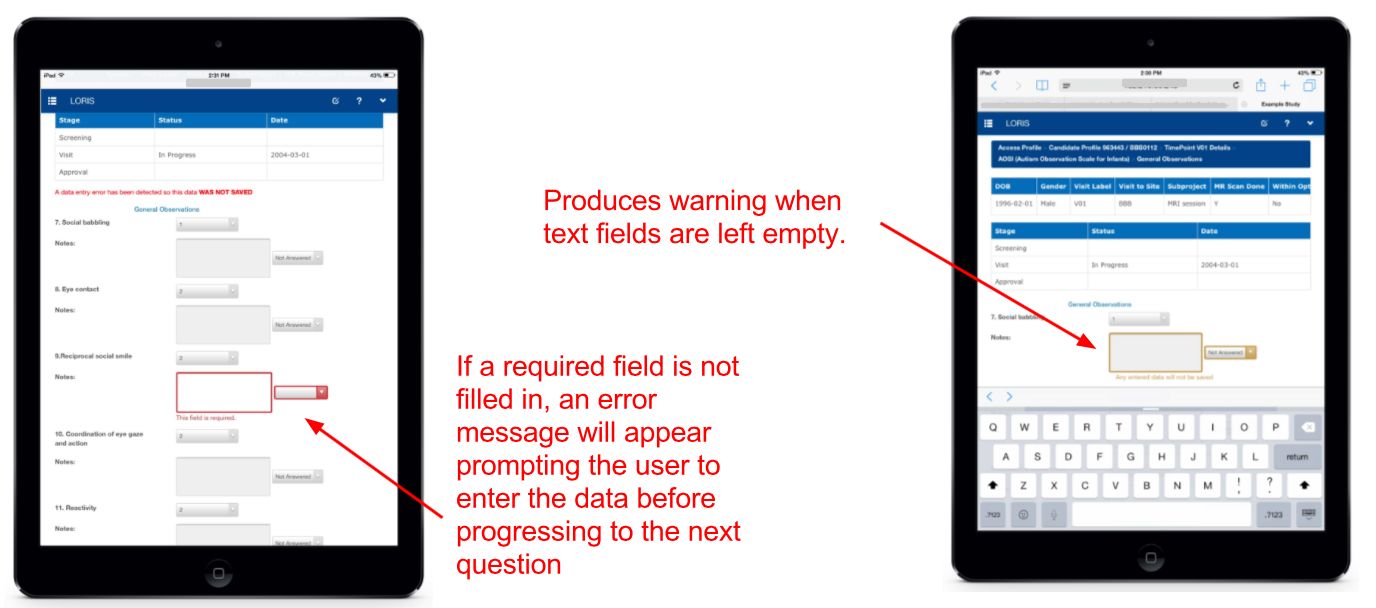

Mobile - Responsive layout

Mobile - Data entry

Tablet Friendly - Survey module